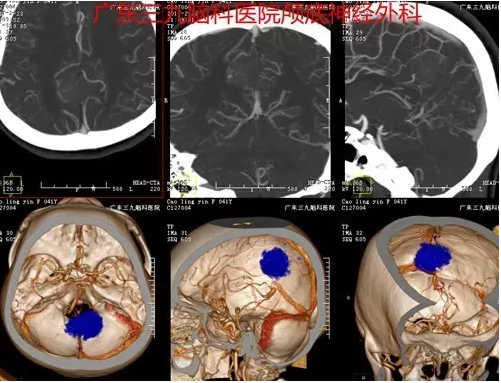

曹某,女性,41岁,因“头痛1月余”前来就诊。入院后完善相关检查,磁共振检查结果提示右侧额顶叶占位性病变,行“右侧大脑镰旁脑膜瘤切除术”,手术顺利,术后磁共振提示肿瘤切除。术后诊断:右侧大脑镰旁脑膜瘤。

图3: CTA提示肿瘤其内血管丰富

据神经外一科刘振业主任介绍,大脑镰旁脑膜瘤是指基底附着于大脑镰或上矢状窦窦腔脑膜瘤,约占颅内脑膜瘤的11%-13%。手术治疗是大脑镰旁脑膜瘤的首选治疗方式。然而,由于镰旁脑膜瘤常常隐藏于大脑皮质下方,并且缺乏早期神经系统症状,导致早期诊断较为困难,一经发现往往肿瘤体积已形成占位效应,并引起如头痛、肢体麻木等神经症状。本例患者为中年女性,以头痛为首发症状,CT示小团状稍高密度影,边界欠清晰,密度尚均匀,血供丰富,MR见病变明显强化,脑膜尾征明显,邻近组织少许片状水肿。